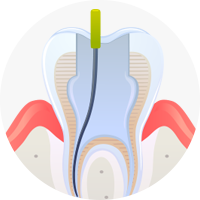

PROCESS·02

PROCESS·02

충치/염증 제거

충치와 뿌리 속 신경 염증을 제거한 후 약제를 이용해 깨끗이 소독을 시행합니다.